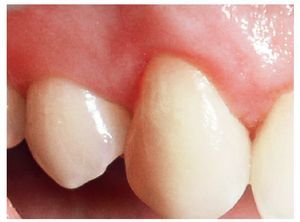

Dos mujeres de 36 y 25 años de edad fueron tratadas por recesiones gingivales en las caras vestibulares de los caninos superiores que les ocasionaban sensibilidad y problemas estéticos (figs. 1 y 2). Las pacientes presentaban buen estado de salud general y no presentaban ninguna contraindicación para la cirugía periodontal. No tenían alergias conocidas a ninguna medicación y negaron consumir alcohol. Tampoco eran fumadoras. Tras un exhaustivo examen clínico, recibieron instrucciones de control de placa y fueron sometidas a limpieza dental profesional en todas las superficies dentarias. Mediante una sonda periodontal manual graduada (CO 15 UNC, Hu-Friedy) se midieron la profundidad de la recesión, la encía queratinizada, profundidad de sondaje, y nivel de inserción clínica.

Figura 1. Aspecto inicial del caso 1.